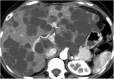

Hamartomas are tumours composed of mesenchymal tissues such as cartilage, fat, connective tissue and smooth muscle and can be found in virtually any organ system. These masses commonly develop sporadically, but are also seen in certain syndromes such as tuberous sclerosis or Carney triad. While their imaging appearance varies depending on the organ they arise from, findings are usually unique and a diagnosis can be confidently made. Radiologists must be aware of the clinical and imaging presentations of these lesions with the particular goal of avoiding unnecessary studies or invasive procedures. Furthermore, knowledge of common syndromic entities is crucial, as the radiologist may be the first to suggest the diagnosis.